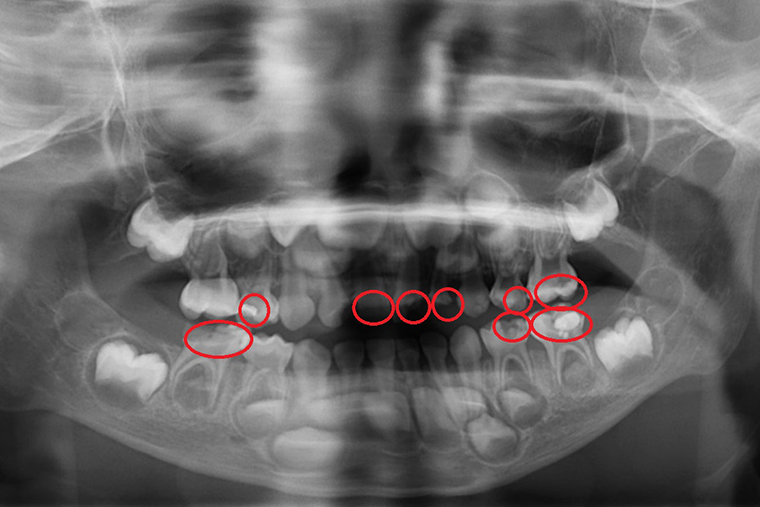

▲X光看見孩子多顆蛀牙(紅圈處均是蛀牙處)。(圖/台北慈濟醫院提供)

【NOW健康 林郁敏/新北報導】一位5歲的小宏在幼兒園定期接受塗氟和口腔檢查,日前卻出現牙痛、臉頰腫脹,台北慈濟醫院兒童牙科醫師陳默檢查發現,小宏罹患嚴重齲齒並已引發蜂窩性組織炎,雖然積極治療,但最後不得不拔除4顆已無法補救的乳牙。陳默醫師對此表示,學校塗氟無法取代完整的牙科檢查與X光診斷,家長應該自孩子長牙後就要定期帶至牙科門診檢查,並掌握5大護牙關鍵,勿等蛀牙惡化才就醫。